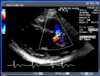

Describe the findings:

*****Dx: HCM with prior apical MI –> LV apical aneurysm

******mid-cavity obliteration during systole –> LVOTO

*******mechanism of MR in this setting –> systolic anterior motion of anterior MV